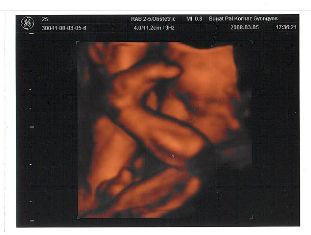

Mátét láthatjátok.

Nagyon szép baba...te vagy az aki biztos lehet benne,hogy nem kell rózsaszín ruha,és lány név :D :D :D :D :D

Melike, nagyon édes Máté baba:)

Melike, nagyon jók a képek Mátéról!!! :lol: